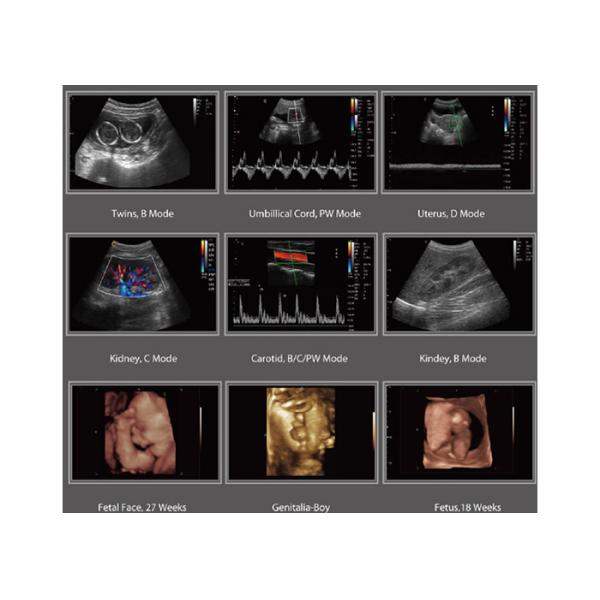

4D Optional Trolley Type Portable Ultrasound Scanner For Clinical Applications Images |